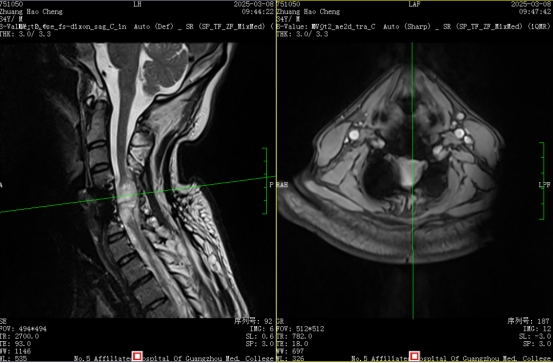

检查结果显示,凌先生颈髓水肿,需要气管插管维持呼吸;双上肢远端肌力仅1级,近端3级;双下肢肌力1级,四肢几乎完全丧失活动能力,仅上臂能轻微摆动。

经过全面评估,广医五院脑科中心团队决定为凌先生实施“脊髓神经刺激器置入术”,通过影像导航将电极精准植入损伤节段。“这就像在断掉的神经线路上架设‘信号中转站’”,杨主任解释,“通过特定频率的微电流刺激,既能阻断异常痛觉信号上传,又能激活残存神经传导功能。”

手术过程很顺利,电极精准放置预定位置。随后医生与工程师根据凌先生的病情和耐受程度对刺激器进行参数调节,给予每天不间断的微电流刺激。